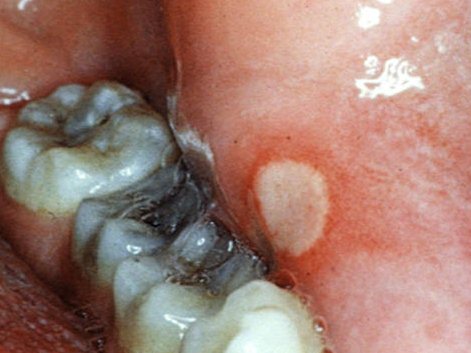

Афтозный стоматит – хроническое заболевание слизистой оболочки ротовой полости. Характеризуется появлением множественных либо единичных афт. Форма афт, как правило, круглая или овальная с характерными границами красной каймы и налетом серо-желтого цвета в центре афты.

Афта – небольшое изъязвление поверхности слизистой оболочки, чаще всего ротовой полости. Афты могут развиваться в виде самостоятельного заболевания (у детей) либо как осложнение другого острого желудочно-кишечного или инфекционного заболевания (гриппа, ящура и т.д.)

Афтозный стоматит — это воспалительное заболевание слизистой оболочки рта, характеризующееся появлением болезненных язвочек (афт). Основные симптомы включают появление одной или нескольких язв, болевые ощущения при приеме пищи, разговоре или чистке зубов, а также возможное покраснение и отек окружающих тканей.